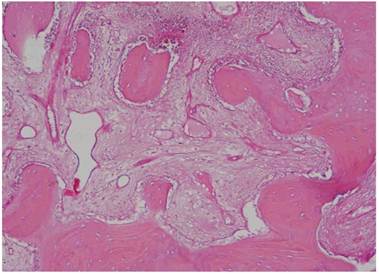

The histological results proved that the samples collected from the “test-side” after 106 days with the adding of PRF “were constituted by lamellar bone tissue with acellular osteocyte lacunae and an intensely-eosinophilic bone matrix mixed with fragments of lamellar bone tissue with inhabited osteocyte lacunae and a slightly-eosinophilic bone matrix (probably to be ascribed to the newly-formed bone tissue). In such fragments, osteocytes are sometimes disposed horizontally and border the bone trabeculae. The interposed stroma is relaxed and richly vascularized” (Figure 1/a - b - c).

Fig 1

a-b-c: Histological pictures referring to Test-Side of “EARLY Protocol”. d: Histological picture referring to Control-Side of “EARLY Protocol”.

Instead, the samples collected from the “Control-Side” revealed that “the fragments were constituted by trabeculae of lamellar bone tissue with inhabited osteocyte lacunae, immersed in a dense poorly-cellular fibrous stroma, in which are included fragments of lamellar bone with empty osteocyte lacunae and with an intensely-eosinophilic bone matrix. We also find roughly globular lacunae, optically empty, probably as a result of the granules of Bio-Oss not yet integrated into the bone matrix”. (Fig. 1/d)